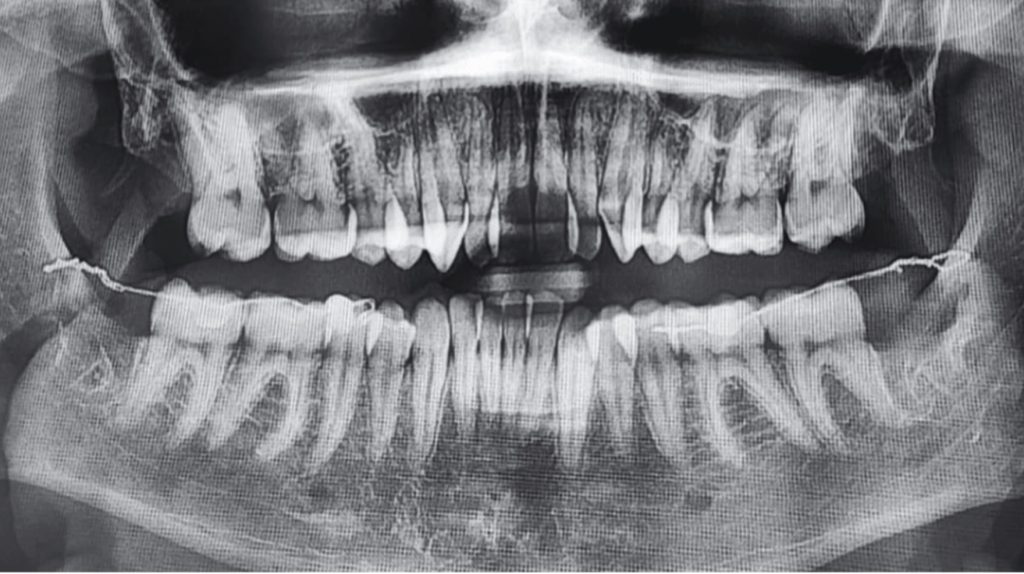

Directo del Journal of Digital Orthodontics les traemos un artículo llamado Severe Class III Malocclusion with Anterior Crossbite and Anterior Crowding: Camouflage Treatment with Premolar Extractions. Los autores nos describen el tratamiento de camuflaje de un hombre de 33 años con maloclusión Clase III esquelética severa (-4.5° ANB), apiñamiento anterior, mordida cruzada y un perfil cóncavo . Debido al rechazo del paciente a la cirugía, optaron por un enfoque ortodóntico .

El tratamiento consistió en la extracción de los segundos premolares maxilares y los primeros premolares mandibulares para generar espacio . Se utilizaron brackets de autoligado pasivos, combinados con tbite-turbos, elásticos Clase III y open coil para corregir la mordida cruzada anterior y retraer el arco mandibular.

Después de 39 meses, se logró un perfil facial y una oclusión satisfactorios . Los resultados incluyeron una mejora de 7° en la inclinación de los incisivos superiores y un mantenimiento del torque inferior, retracción mandibular de 8 mm y del labio inferior de 4 mm. ¿Como llegaron a eso? Muy fácil…